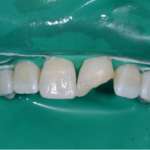

Restauro vestibolare micro-invasivo (Approccio multidisciplinare)

Questo interessante video presenta la realizzazione di un restauro vestibolare estetico eseguito tramite un approccio multidisciplinare che prevede la realizzazione di un lembo di...